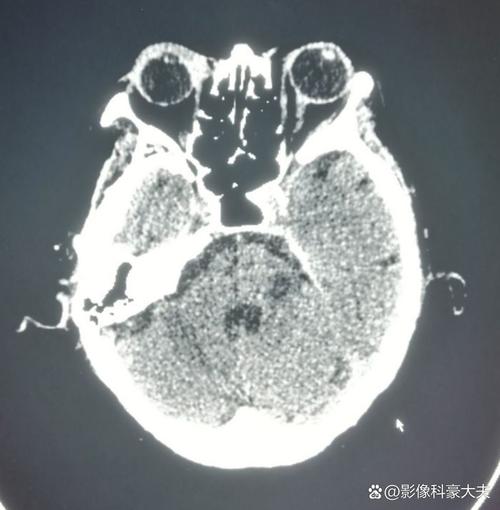

这是一个非常重要且紧急的医疗问题,脑梗导致脸麻,最常见和最典型的梗塞位置是大脑半球的特定区域,尤其是大脑中动脉的供血区域。

负责控制对侧脸部感觉和运动的神经中枢出现了缺血性坏死。

最关键的供血血管:大脑中动脉

上述提到的这些关键区域(大脑皮层的感觉和运动中枢、内囊)主要由大脑中动脉及其分支来供血。

大脑中动脉闭塞或狭窄是导致脑梗脸麻的最常见原因,大脑中动脉是大脑半球最主要的供血血管,梗塞后影响的范围广,症状也通常比较典型和严重。

脑梗导致脸麻,最常见的是对侧大脑半球的感觉中枢或运动中枢发生了梗塞,其幕后“元凶”通常是大脑中动脉的阻塞,任何原因不明的脸部麻木,都应被视为脑卒中的高危信号,必须立即寻求紧急医疗救助。